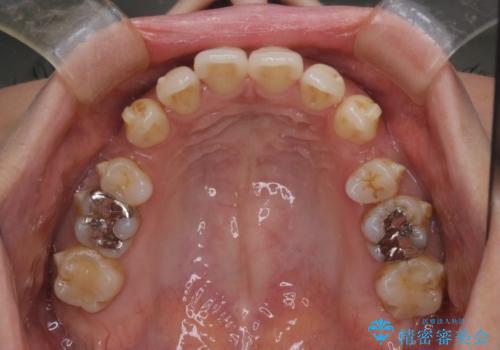

- 上の前歯の突出感を気にして来院された患者様です。

目立たない装置を希望とのことで、上顎左右第一小臼歯を抜歯し、インビザラインにて矯正治療を行うこととしました。